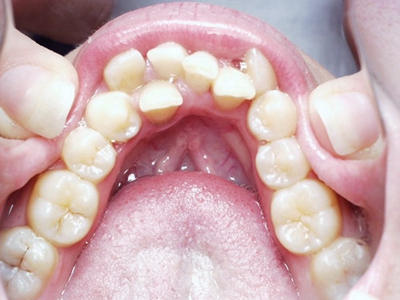

阻生牙是指由于邻牙、骨或软组织的阻碍而只能部分萌出或完全不能萌出,且以后也不能萌出的牙。引起牙阻生的成因,主要是由于颌骨缺乏足够的空间容纳全部恒牙。常见的阻生牙为下颌第三磨牙、上颌第三磨牙及上颌尖牙。

阻生牙主要原因是随着人类的进化,颌骨的退化与牙量的退化不一致,导致骨量相对小于牙量,颌骨缺乏足够的空间容纳全部恒牙。